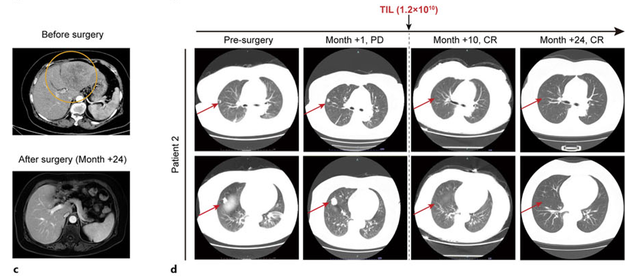

患者二:67岁女性,同样因肿瘤破裂出血入院,左肝肿瘤巨大(约14.7×7.9cm),双肺多发转移,AFP为14529 ng/mL。

患者二:在术后1个月时,肺部病灶曾进展(从18mm增大到25mm),但在TIL联合规律抗PD-1治疗下,术后10个月,所有肺转移灶完全消失,并长期维持无瘤状态。

图片来源于Karger

截至报告时,这两位晚期肝癌患者已分别无瘤生存超过24个月和48个月,且生活质量良好,无需任何额外抗肿瘤治疗。